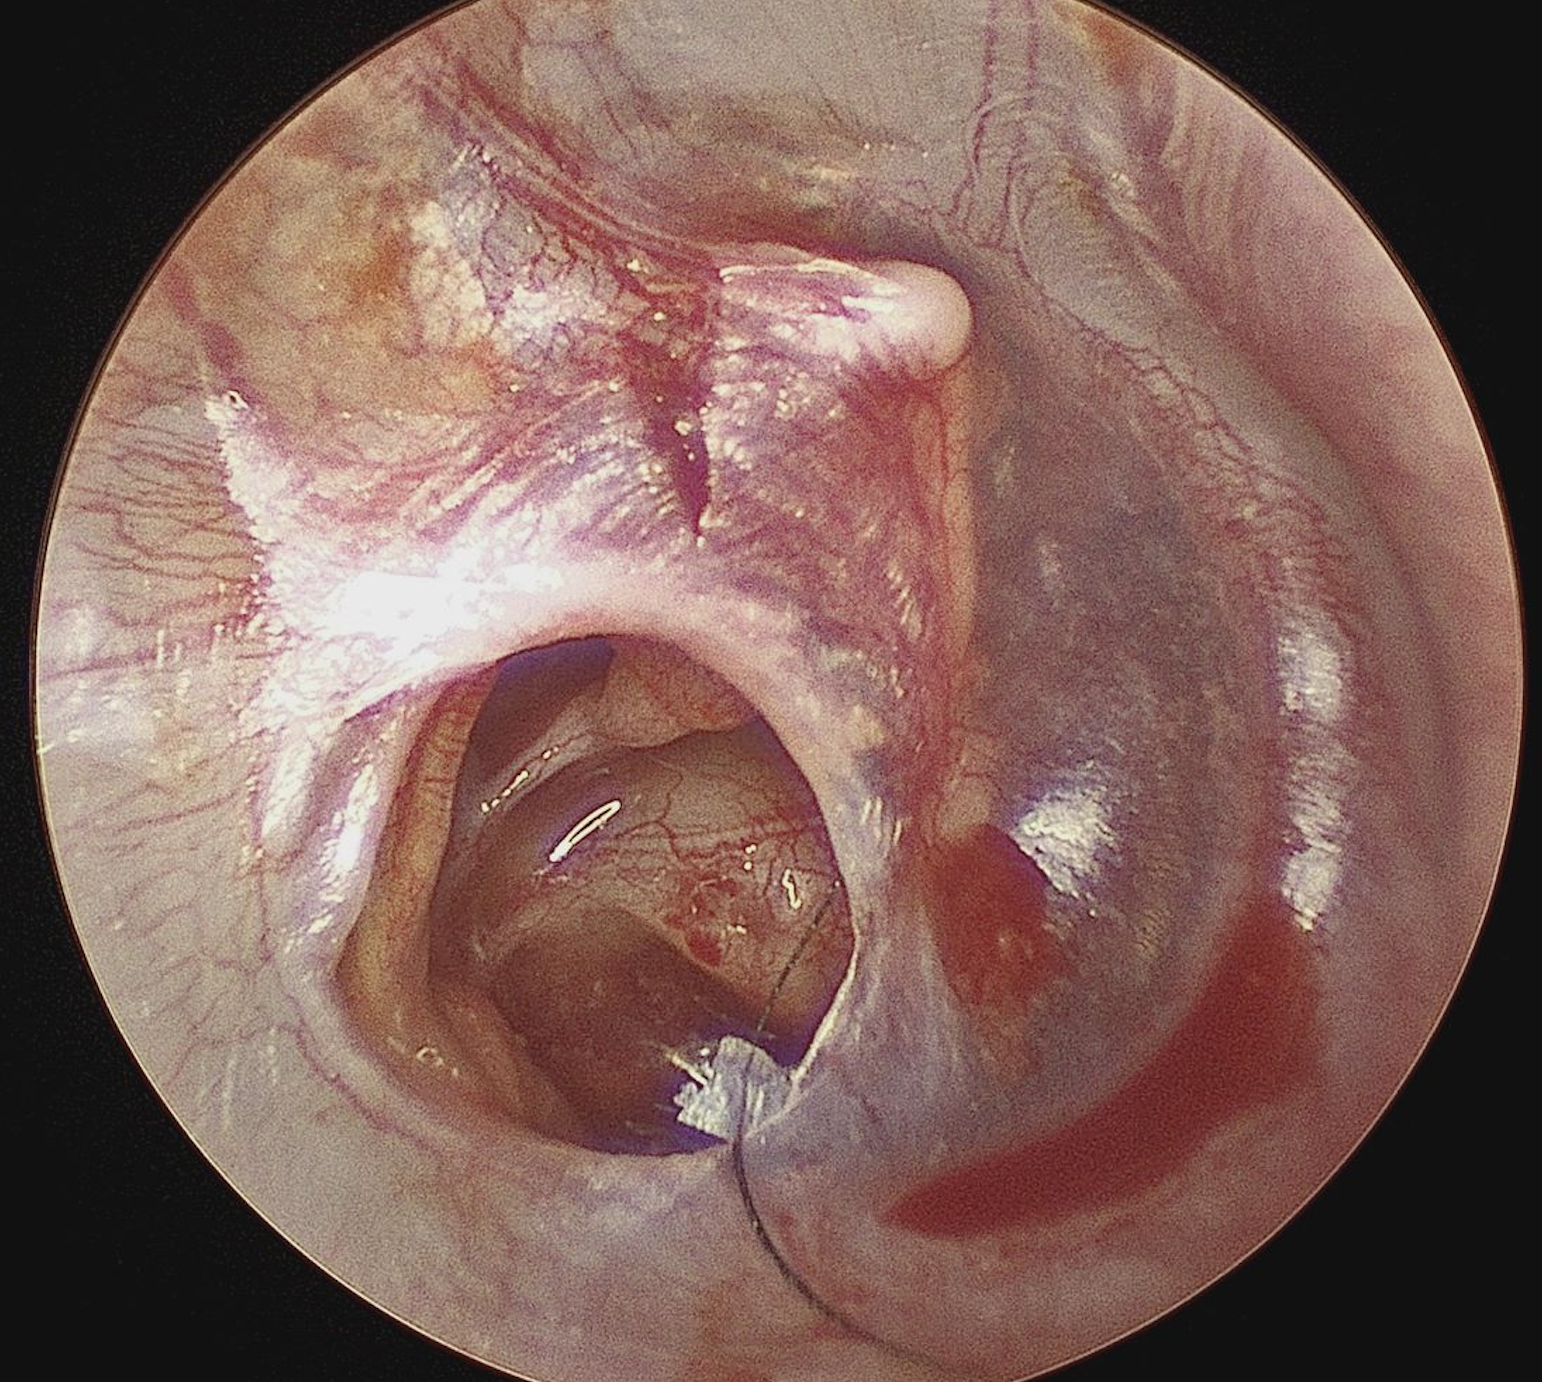

Perforated ear drum (right ear) with view of incus and stapes bones in middle ear

Hearing is important, and issues like eardrum perforations can significantly impact this ability, leading to hearing loss and recurrent ear infections. This is where tympanoplasty, a surgical treatment for an abnormal ear drum, steps in. Designed to repair a perforated tympanic membrane (eardrum) and/or reconstruct the middle ear's small bones (ossicles), tympanoplasty aims to restore hearing and prevent further infections.

Tympanoplasty is a specialized surgical procedure focused on repairing the damaged eardrum and, if necessary, the ossicles in the middle ear. The procedure varies in complexity, tailored to address the specific needs of each patient, whether it's patching up a simple perforation or undertaking a more complex reconstruction of the middle ear structures with removal of cholesteatoma.